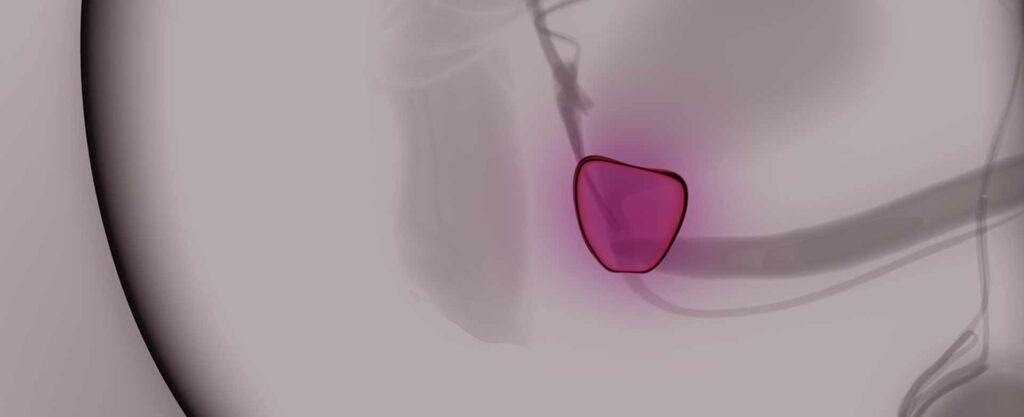

MRT-TRUS-Fusion: Unlängst haben wir unsere Diagnostikmethoden für die Prostata um die sogenannte MRT-TRUS-Fusionsbildgebung verbessert. Hierbei handelt es sich um eine Zusammenführung von Bilddaten aus der transrektalen Ultraschalluntersuchung der Prostata (TRUS) und der Magnetresonaztomographie (MRT, auch Kernspintomographie) der Prostata in einem speziellen medizinischen Gerät. Durch die Zusammenführung der Bilddaten ist es möglich sämtliche Auffälligkeiten beider Untersuchungsverfahren in Echtzeit zu überprüfen, zu Vergleichen und gegebenenfalls Zielgenau zu punktieren (siehe hierzu auch Uro-News vom 11.07.2016)

Wir bieten dieses Konzept der Active surveillance seit mehreren Jahren mit gutem Erfolg für unsere Patienten an. Wir bedienen uns dabei zusätzlicher bildgebender (Elastographie, Kernspinntomographie, MRT-TRUS-Fusion) und molekular-genetischer Marker (Prolaris Test, PCA3 Test). Die Patienten werde regelmäßig untersucht, so dass kein unbemerktes Tumorfortschreiten eintritt.